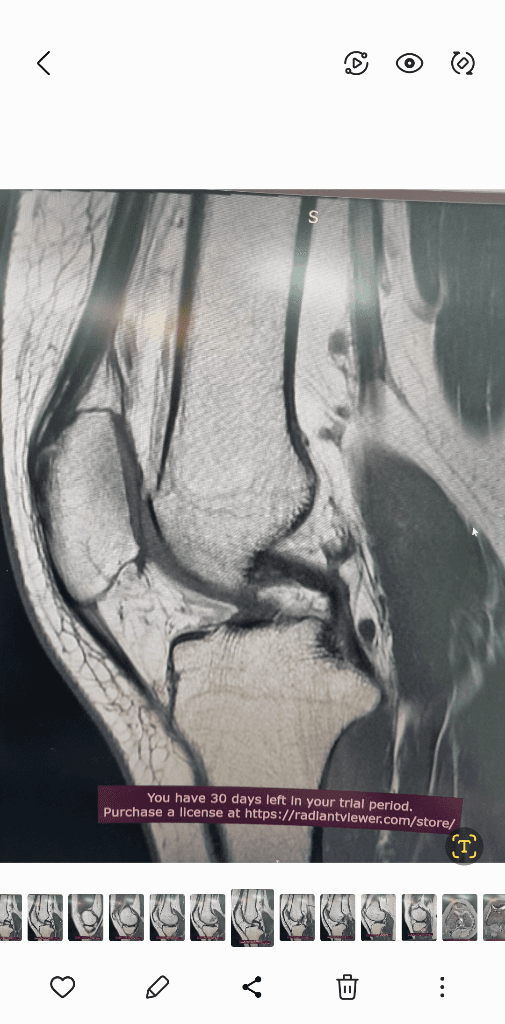

1. 추벽이 아닙니다.

2. 슬개골 관절면에 외상으로 인한 골수부종입니다.

3. 관절면 손상여부는 첨부해주신 영상만으로 알 수 없습니다